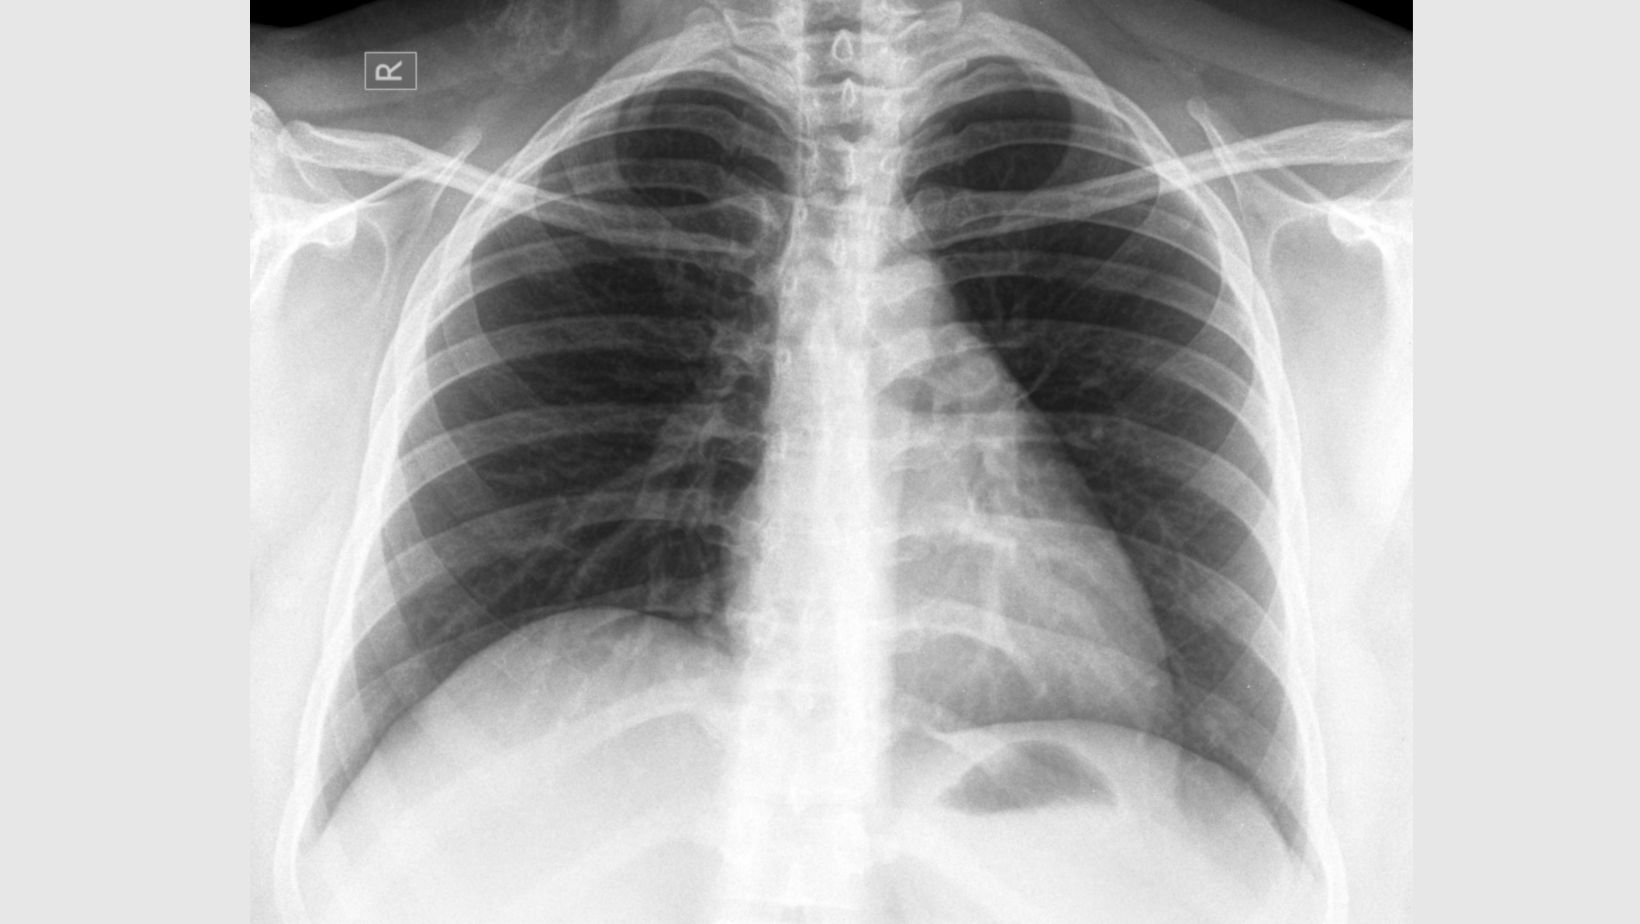

흡연 경험이 없더라도 만성 폐 질환 병력이 있는 경우 폐암 발병 위험이 3배 가까이 증가하는 것으로 나타났다.

그 결과 비흡연자 폐암 발병의 가장 강력한 위험인자는 ‘만성 폐 질환 유무’인 것으로 나타났다.

비흡연 환자 중에서 폐결핵 등 폐 관련 질환 병력이 있는 경우 폐암 발병 위험이 대조군보다 2.91배 높았다.

특히 만성폐쇄성폐질환(COPD) 환자의 경우 폐암에 걸릴 위험이 7.26배까지 올라갔다. 연구진은 이러한 위험이 폐에서 계속되는 만성적 염증 반응 때문일 것으로 추정했다.